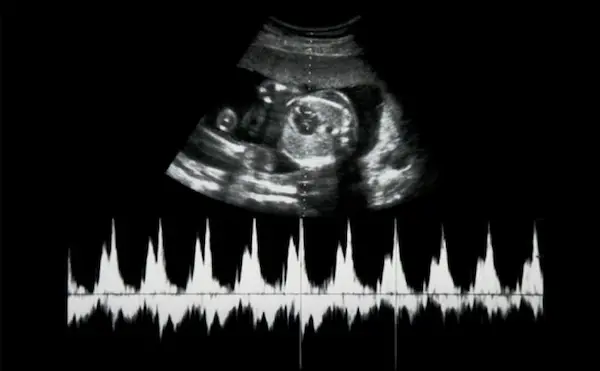

ويبدأ نبض الجنين كصوت خافت يشبه طقطقة الطبلة الصغيرة، ثم يتسارع تدريجيًا مع التقدم في الحمل. ويعد مؤشرًا دقيقًا يكشف عن صحة الجنين، ونموه السليم.

يعد بدأ نبض قلب الجنين من أهم مراحل نموه. ويبدأ نسيج القلب بالنبض في حوالي الأسبوع الخامس، أو السادس من الحمل، ويسجل على الموجات فوق الصوتية كنبضة قلب، على الرغم من أن القلب لم يتطور بعد.

يقيس الطبيب معدل نبض قلب الجنين من خلال عدد النبضات في الدقيقة أثناء الحمل، ويساهم ذلك القياس على تقييم حالة الجنين أثناء زيارات ما قبل الولادة، أو المخاض.

ويتراوح معدل ضربات قلب الجنين الطبيعي بين 110 إلى 160 نبضة في الدقيقة. في المراحل المبكرة جدًا من الحمل يكون حوالي 110 نبضة في الدقيقة.

قد يزداد معدل ضربات قلب الجنين ليصل إلى 170 نبضة في الدقيقة في الأسبوع التاسع تقريبًا، ثم يتباطأ إلى حوالي 110 نبضة في الدقيقة بعد ذلك.

1- الموجات فوق الصوتية

قد تخضع الحامل لفحص بالموجات فوق الصوتية؛ للكشف عن نبض قلب الجنين في مراحل مختلفة من الحمل. وقد يوصي الطبيب بإجراء فحص مبكر يصل إلى ستة أسابيع إذا كانت الحامل تعاني أي نزيف، أو مشكلات في حمل سابق.